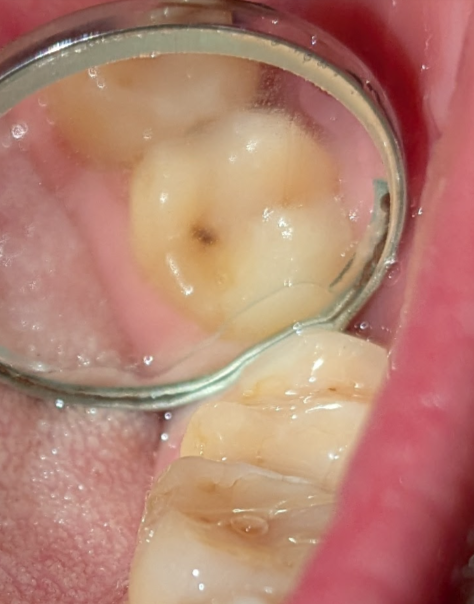

kurz und knapp ein paar Fotos. Karies oder nicht?

vermutlich nicht

würde dennoch bitewing machen